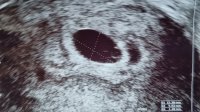

Så herlig å kunne puste litt ut!6+5 i dag, og lille frø måler ca 4,5 mm. Så hjerteslag, men gynekologen var så stressa - at vedkommende knapt gadd å se i 1,5 minutt før prosessen ble avslutta. Ville ikke skru på doppler for å høre hjertelyd heller, sa bare «jeg gjør ikke sånn så tidlig jeg». Uten mer forklaring

Jaja, vi er uansett kjempe happy. Og puster nå litt letta ut